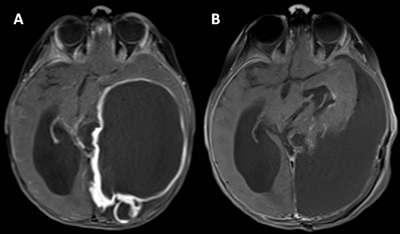

A previously healthy 12-month-old female presented with a 3-week history of developmental regression, intermittent seizures, and truncal ataxia. Physical examination revealed hypotonia, generalized hyporeflexia, and a head circumference greater than the 99th percentile for age. Brain imaging demonstrated a large left parieto-occipital intraparenchymal mass with cystic and solid components, heterogeneous contrast enhancement, and signs of hydrocephalus with uncal herniation secondary to mass effect (Figure 1A). There were small areas of meningeal contact in the mesial left parieto-occipital regions, but no meningeal thickening or enhancement were present. Urgent craniotomy was performed with successful gross total resection of the mass (Figure 1B). Staging procedures were performed, and tumor was determined to be localized based on negative spine MRI and clear CSF on lumbar puncture (performed > 14 days after resection).

Figure 1

A. Brain MRI (post-contrast axial T1-weighted) revealed a contrast-enhancing left parieto-occipital mass (11.5 x 7.4 x 8.2 cm) with mixed cystic and solid components. The tumor abuts the leptomeninges but there is no meningeal thickening or enhancement. There is secondary hydrocephalus and midline shift resulting from the mass effect. B. Post-operative imaging (post-contrast axial T1-weighted) showing gross total resection of the mass.